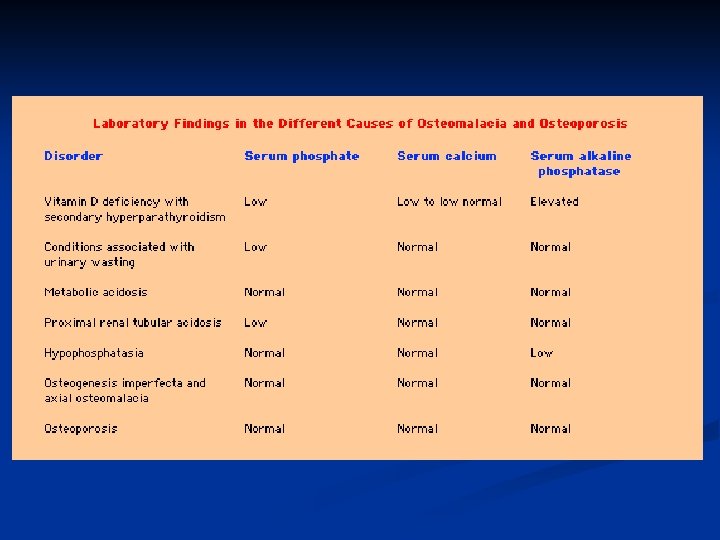

RICKETS, OSTEOMALACIA INVESTIGATIONS: BLOOD TESTS Calcium Reduced, Phosphate reduced Alkalline Phosphatase increased Urinary excretion of calcium diminished Calcium phosphate products (= serum [Ca] x serum [PO 4]) normally 30. In rickets and osteomalacia is less than 24

Osteomalacia & Rickets Diagnosis n Other laboratory abnormalities may include Hypocalcemia n Hypophosphatemia n Elevated serum alkaline phosphatase n

Biochemical findings in rickets n Alkaline phosphatase usually is ↑in all forms of rickets. n Serum phosphorus concentrations usually are↓ in both hypocalcemic and hypophosphatemic rickets. n Serum Ca is ↓only in hypocalcemic rickets. n Serum parathyroid hormone typically is ↑in hypocalcemic rickets, in contrast it is N in hypophosphatemic rickets. n 25 -OH vitamin D reflect the amount of vitamin D stored in the body, and is ↓in vit D deficiency. n 1, 25 -OH 2 vitamin D can be↓, N or ↑in hypocalcemic rickets and usually is N or slightly ↑in hypophosphatemic rickets.

Laboratory findings in Osteomalacia Decreased serum calcium levels n Decreased serum phosphorus levels n Elevated serum alkaline phosphatase n Xrays show bone demineralization n

Laboratory findings in Osteomalacia Decreased serum calcium levels n Decreased serum phosphorus levels n Elevated serum alkaline phosphatase n Xrays show bone demineralization n